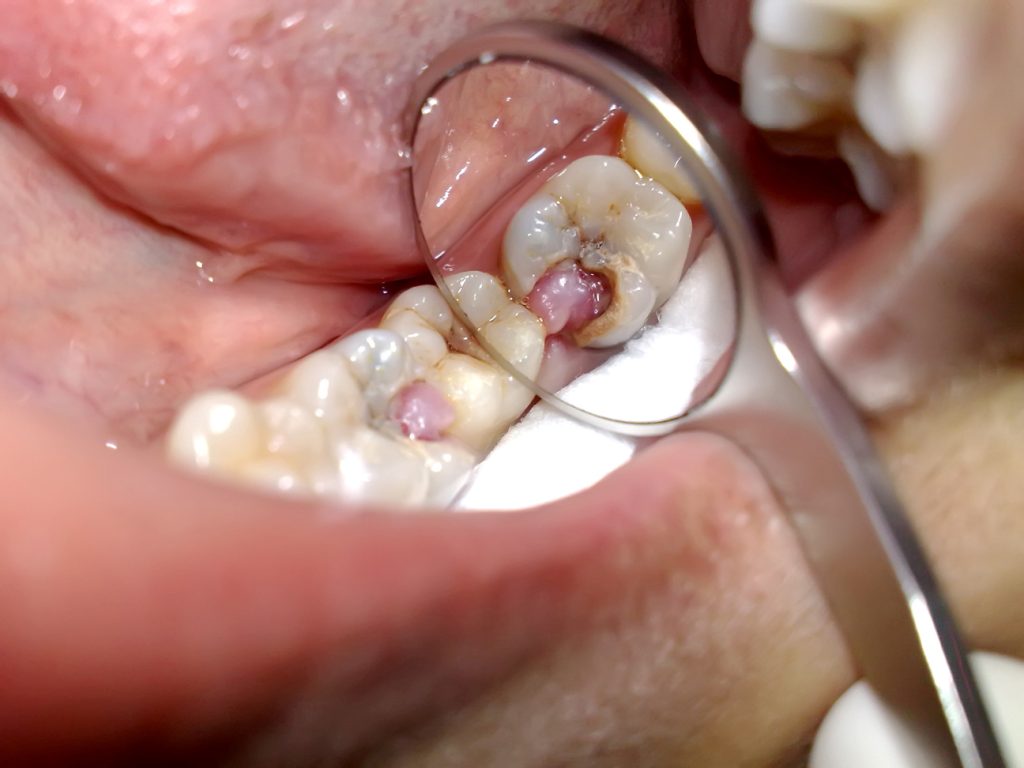

- Deep Cavities: Decay that has reached or is very close to the pulp chamber, allowing bacteria to invade.

- Cracked or Fractured Teeth: Cracks that extend deep into the pulp, creating a pathway for bacteria.

- Swelling: In later stages, swelling around the affected tooth or a small pimple-like bump on the gums (fistula) may indicate an infection spreading.

- Root Canal Therapy: Root canal treatment is the most common and effective irreversible pulpitis treatment. The inflamed or infected pulp is removed, the inside of the tooth is cleaned and disinfected, and then filled and sealed. The tooth is often capped with a dental crown to protect it.